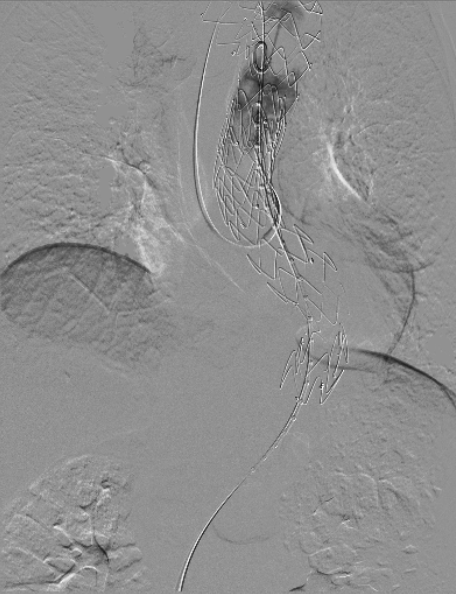

患者平躺后行全麻手术,穿刺双侧股动脉,导入造影导管并进行DSA造影,造影后确认与术前检查结果一致;

治疗车怎么推「弓部重建直通车」鄂尔多斯市中心医院康巴什部介入科运用Castor®分支型支架联合预开窗技术治疗Stanford B型胸主动夹层_https://www.jmylbn.com_新闻资讯_第6张

术前造影